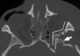

Fracture with retro-orbital hematoma

Unilateral exophthalmos